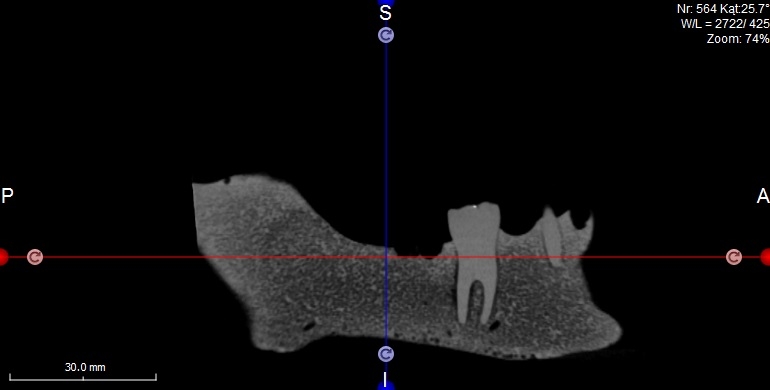

Oferujemy również szablony chirurgiczne przeznaczone do szkoleń z implantacji. Umożliwiają planowanie leczenia implantologicznego i przeprowadzenie szkoleń z wykorzystaniem plików CT, STL oraz druku 3D. Oferujemy nasze modele do szkoleń implantologicznych wraz z plikami DICOM i STL.

Pliki do wykonania szablonów można pobrać z naszej strony internetowej. Możemy je również dostarczyć wraz z modelami. Pliki te dostępne są dla modeli 10-1030, 10-3040, 10-3050, 10-5070,